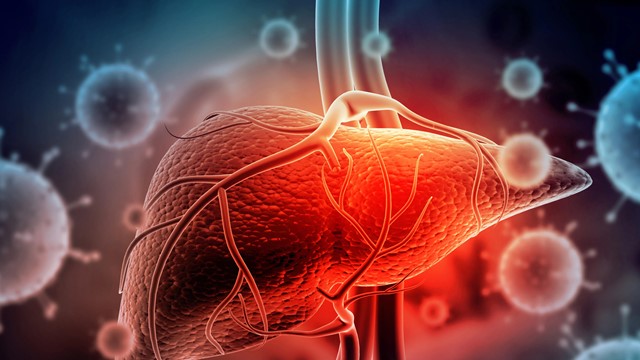

Virus ‘sát thủ’ lây nhanh gấp 100 lần HIV, Việt Nam thuộc nhóm có tỷ lệ nhiễm cao nhất khu vực

(Thị trường tài chính) - Loại virus này có thể tồn tại bên ngoài cơ thể người ít nhất 7 ngày, nhưng vẫn đủ sức gây bệnh nếu xâm nhập vào người chưa được tiêm phòng.